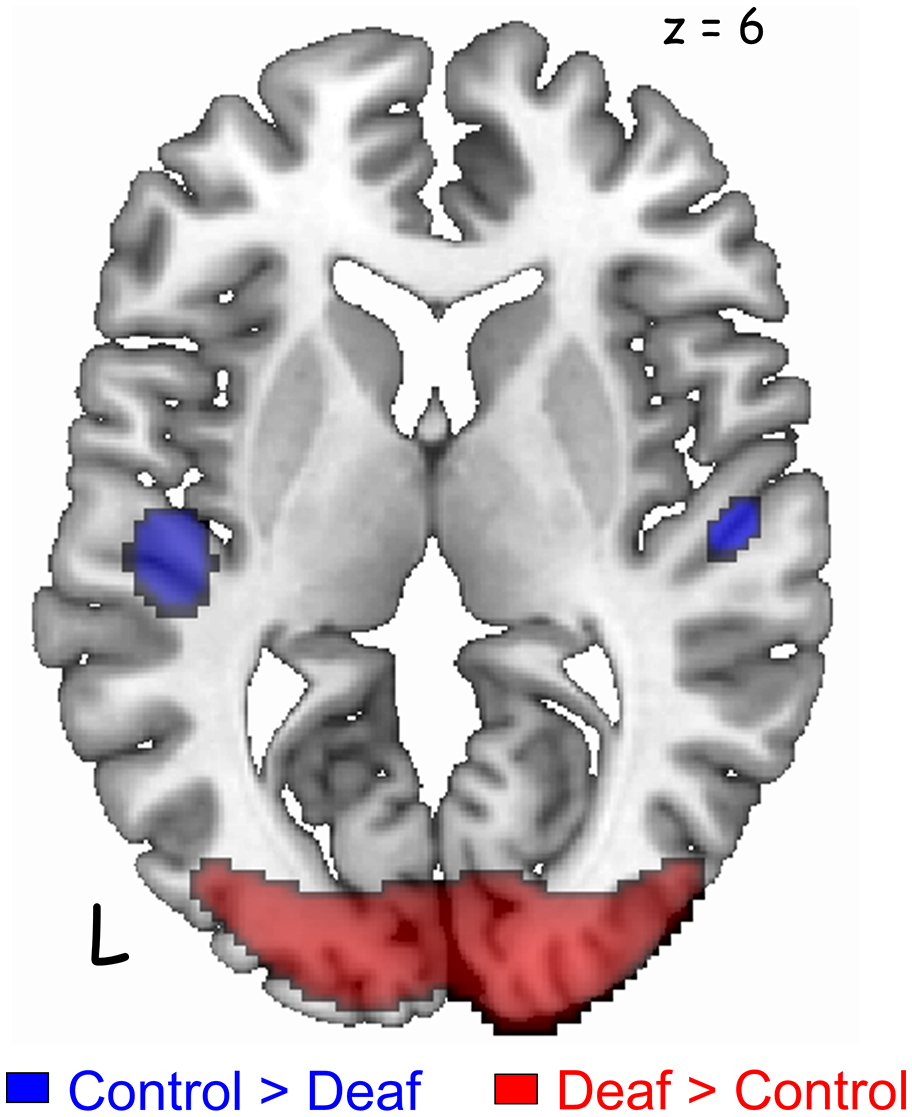

Group Comparison

The deaf group showed decreased metabolism in regions of the auditory pathway, including the inferior colliculus and the bilateral superior temporal gyrus (Table 2, Figure 2). However, the metabolism in the right temporal gyrus of the deaf patient group was not significantly different with the NH group (40 voxels with uncorrected p = 0.0005), but survived following a small volume correction (SVC; 5 mm sphere at peak voxel, FWE-corrected p = 0.001). For the deaf group, the cerebral glucose metabolism was significantly higher in the bilateral calcarine gyri and the right posterior middle temporal gyrus (BA 39), while the metabolism was lower in areas of the bilateral dorsal cingulate gyri (Table 2).

FIGURE 2

www.frontiersin.org

Figure 2. Significant differences in the auditory and visual cortices between the groups [p < 0.05, family-wise error rate (FWE)-corrected for multiple comparisons]. Deaf patients showed decreased metabolism in the bilateral auditory cortices (blue) and increased metabolism in the visual cortex (red). A cluster in the right auditory cortex survived after small volume correction (SVC) with a corrected p-value of 0.001.